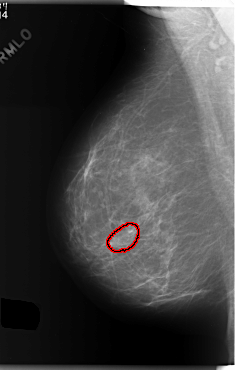

C_0169_1.RIGHT_MLO

RIGHT_MLO LINES 5912 PIXELS_PER_LINE 3760 BITS_PER_PIXEL 12 RESOLUTION 50 OVERLAY

FILE: C_0169_1.RIGHT_MLO.OVERLAY

TOTAL_ABNORMALITIES 1

ABNORMALITY 1

LESION_TYPE CALCIFICATION TYPE AMORPHOUS DISTRIBUTION CLUSTERED

ASSESSMENT 4

SUBTLETY 2

PATHOLOGY MALIGNANT

TOTAL_OUTLINES 1

BOUNDARY